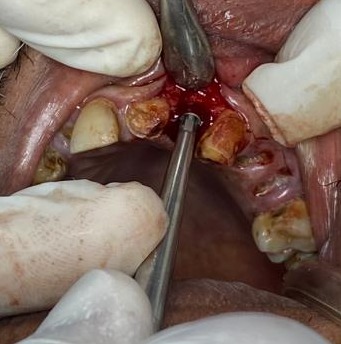

CASE BY DR. SMIJAL --NARROW RIDGE

Drilling in this situation will create disaster .

CASE BY DR. SMIJAL --No drill osteotomy with OSSEOSURE

OSSEOSURE is used to create nice osteotomy . Angulation corrected easily with osseosure tips.